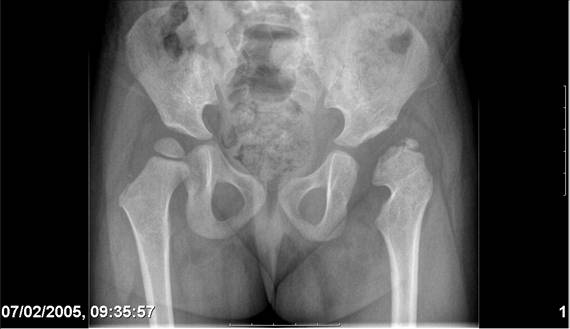

Navernoe Dega

Chto by ne byt goloslovnym posilau vam svoi sluchai gde sdelal vse chto napisal vyshe